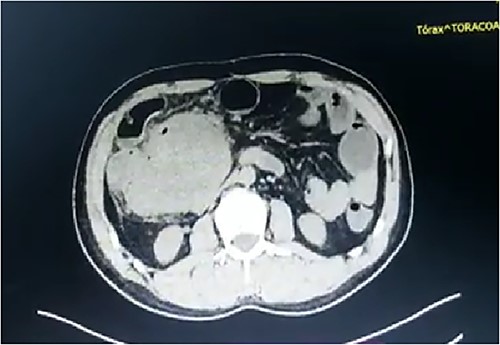

A 43-year-old man underwent exploratory laparotomy for acute appendicitis 11 months prior to this presentation in which a mesenteric mass was detected perioperatively. The patient presented to our center with a 24-h history of colicky, diffuse abdominal pain without an apparent cause that was of moderate intensity and accompanied by nausea and vomiting on various occasions. Physical examination revealed a complaining patient with a distended abdomen that was painful on palpation at the right hypochondriac region and right iliac fossa. A fixed mass measuring 10 cm in diameter was palpated in the right inferior quadrant and bowel sounds were increased. Biometric screening results and the urea creatinine ratio were normal. Tumor markers including CA 19–9, alpha-fetoprotein and carcinoembryonic antigen levels were within the normal range. Abdominal computed tomography with and without contrast showed a solid intra-abdominal mas at the right paraumbilical level measuring 70 mm in the largest diameter and adjacent to the right colon. The mass was round and had a regular, well-defined contour with signs of central necrosis, compressing the distal segment of the small intestine (Fig. 1). Colonoscopy was normal.

Abdominal computed tomography showing an intra-abdominal mass measuring 70 mm in diameter and compressing the small intestine.